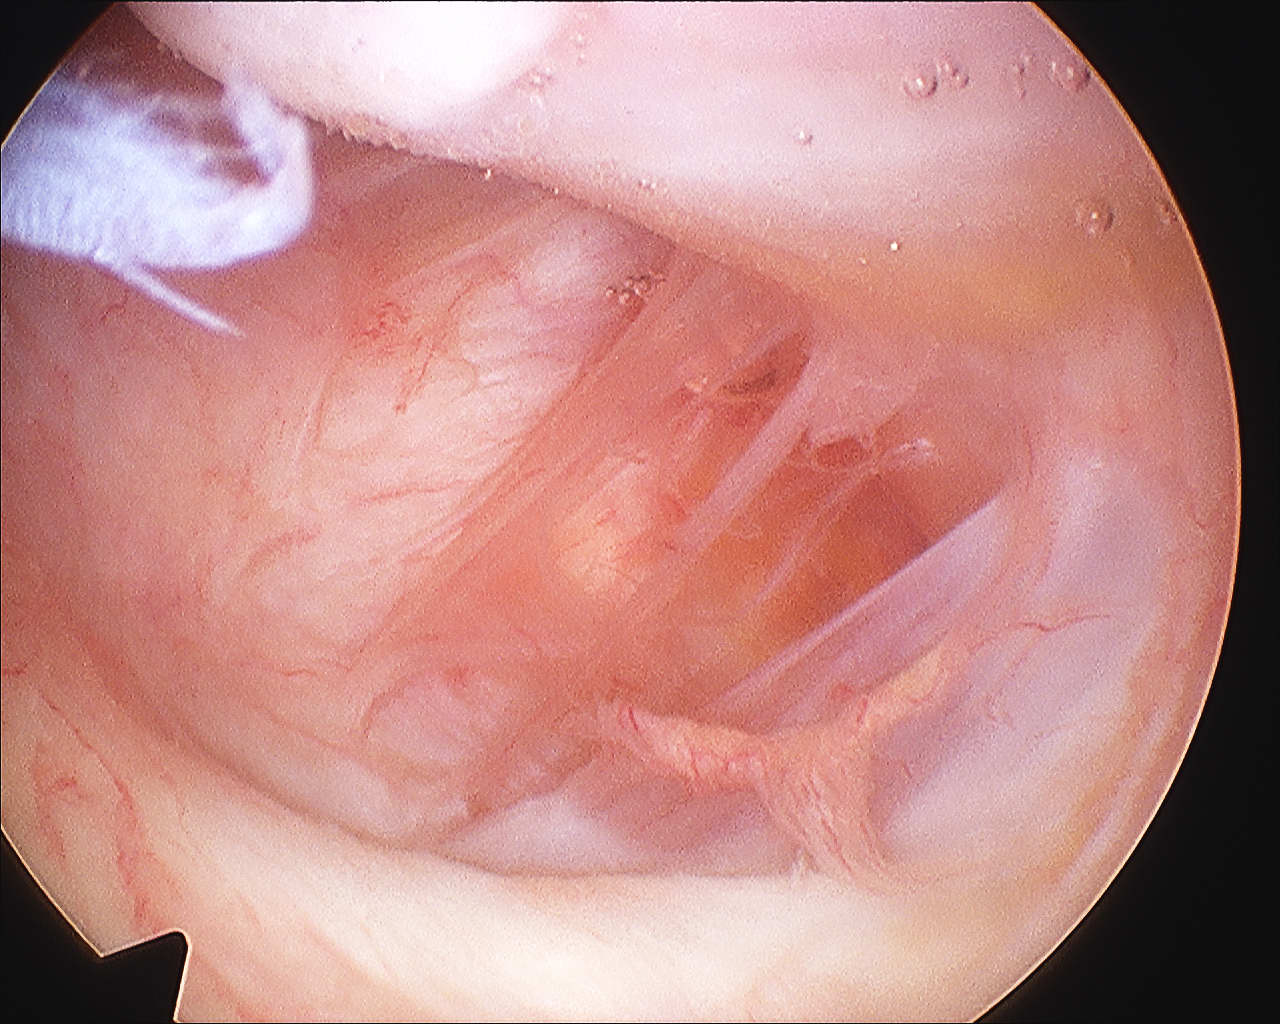

Arthroscopy

Normal insertion onto humeral neck

Normal Humeral Attachment IGHLHAGL

Abnormal

HAGLHAGL